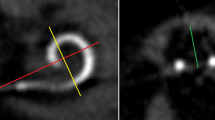

Postoperative imaging was performed using a DynaCT-equipped Axium Artis dTA angiography unit (Siemens Co., Erlangen, Germany) with a digital flat-panel detector [3, 7]. Two experienced head and neck surgeons and two head and neck radiologists independently analyzed the scans regarding scalar electrode position (ST versus SV insertion, intracochlear dislocation, angular insertion depth) and cochlear size (diameters in length and width) and used Impax 6 from Agfa Healthcare for reconstruction. The scans were not evaluated by the surgeons who, performed the CI surgery but by independent and experienced head and neck surgeons to reduce bias. All included electrode arrays were fully inserted. Cochlear size was evaluated in distance A from the round window to the lateral wall through the modiolus and perpendicular distance B [1, 2, 8]. The angular insertion depth was evaluated between the vectors of distance A and the distance through the bloom artefact of the apical electrode and the modiolus as described before [2, 8, 9]. Dislocation analysis and analysis of scalar position were performed on three-dimensionally reconstructed cross-sectional images as previously described [2, 8], i.e. the 3D-reconstruction could be rotated and browsed in whichever direction the specialists needed to come to their respective conclusion. Every image with discrepancy was reviewed and discussed interdisciplinary until a final agreement and measurement was achieved.

Figure 2 shows the mean angular insertion depth for each included electrode array. Regarding the included Cochlear™ electrode arrays, we measured a significantly higher angular insertion depth for the SSA compared to the CA (p = 0.0004). The angular insertion depth was comparable between the CA and the SMA (p = 0.15) or between the SSA and the SMA (p = 0.9996). Regarding the electrode arrays from MED-EL, the Flex24 showed significantly lower angular insertion depth compared to the longer electrode arrays Flex28 and FlexSoft (p < 0.00001) as expected. All included electrode arrays from Cochlear™ showed significantly shorter angular insertion depth than the electrode arrays from MED-EL (p in all comparisons < 0.0065) (see Fig. 2).

Measuring the specific position of dislocation for each electrode array, we found that the position of dislocation depends on the electrode array itself (see Fig. 4). We measured a significant lower point of dislocation for the CA compared to both the Flex28 (p < 0.00001) and the FlexSoft (p < 0.00001). The point of dislocation is electrode-design specific. Perimodiolar electrode arrays dislocate between 160 and 180° (CA: mean ± SD: 170 ± 25°), whereas straight electrode arrays dislocate between 280° and 330° (Flex28: mean ± SD: 284 ± 87°; FlexSoft: mean ± SD: 330 ± 36°).

We could measure specific angular insertion depth for each included electrode array (see Fig. 2). Previous studies [1, 2] showed that the angular insertion depth is dependent on the cochlear size. This work extends the earlier studies by defining electrode array-specific angular insertion depth, depending on both electrode array design and cochlear morphology.

We could show that the position of dislocation is electrode-design specific (see Fig. 4) and depends on electrode array design itself. The SSA has a stiff internal stylet and is a lateral wall array. Therefore, the dislocation point is more apical than the dislocation point of the perimodiolar CA. The CA is inserted via an Advance Off–Stylet™ insertion technique and due to its preformed perimodiolar design the point when dislocation might happen is earlier and at approximately 180°. Further studies described the ascending cochlear basal turn at around 180° as sensitive for scalar dislocation [13,14,15]. Aschendorff et al. [7] speculated that perimodiolar electrode arrays may touch the outer cochlear wall at 180° while rotating with an upward direction and being pushed forward, resulting in perforation of the basilar membrane.

With a maximal active length of 25 mm (source: Cochlear™), the SSA is shorter than the straight Flex28 and FlexSoft and shows less insertion depth. MED EL electrode arrays do not have such a rigid internal stylet as the SSA. Therefore, the point of dislocation is higher in longer and more flexible MED EL Flex28 and FlexSoft due to their flexibility and trajectory. Furthermore, the height of the ST decreases within the ascending part of the basal turn towards the apical cochlear part [16]. Therefore, long electrode arrays like the Flex28 and FlexSoft showed increasing risk of dislocation in the apical cochlear part. The fact that the Flex24 showed the highest dislocation point is interesting but since there was only one dislocated Flex24 array further studies are required.